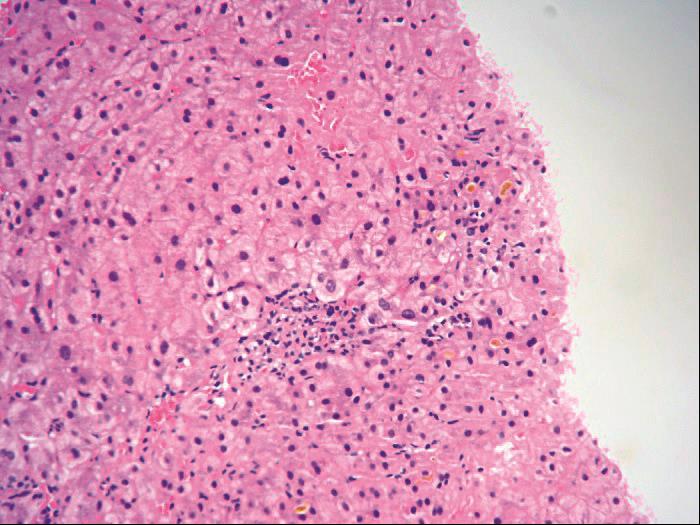

图4-3-4 酒精性肝病

酒精性肝纤维化,广泛肝血窦周围纤维化,纤维间隔形成,小叶结构紊乱(Masson染色)